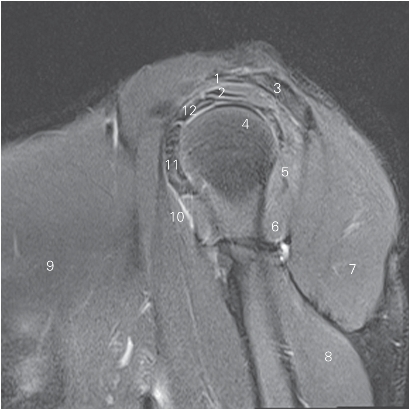

图4-20 经肱二头肌短头的矢状断层MR T2WI FS

1 喙肩韧带 coracoacromial ligament 2 冈上肌 supraspinatus

3 肩胛冈 spine of scapula 4 肱骨头 head of humerus

5 冈下肌 infraspinatus 6 小圆肌 teres minor

7 三角肌 deltoid 8 肱三头肌 triceps brachii

9 胸大肌 pectoralis major

10 肱二头肌短头 short head of biceps brachii

11 肩胛下肌 subscapularis

12 肱二头肌长头 long head of biceps brachii